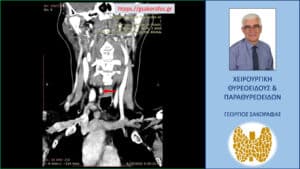

Λόγω επιμένοντος PHPT και με δεδομένους τους περιορισμούς των δύο βασικών διαγνωστικών εξετάσεων (υπερηχογράφημα και σπινθηρογράφημα) παραπέμφθηκε για περαιτέρω έλεγχο με τετραδιάσταση αξονική τομογραφία (4D-CT) όπου περιγράφεται μόρφωμα με διαστάσεις 9 x 7.5 x 5 mm παρά τον οισοφάγο, σε επαφή με την προσπονδυλική περιτονία, στο ύψος του Α6 σπονδύλου, πίσω από την τραχεία και την δεξιά κοινή καρωτίδα.

H εικόνα είναι συμβατή με έκτοπο αδένωμα παραθυρεοειδούς.

Απεικόνιση του αδενώματος στην 4D-CT – κατά μέτωπο διατομή (κόκκινο βέλος)

Απεικόνιση του αδενώματος (κόκκινο βέλος) σε κατά μέτωπο διατομή στην 4D-CT σε διαφορετικό επίπεδο. Απεικονίζεται σε παρακείμενη θέση και ο οισοφάγος (κίτρινο βέλος)